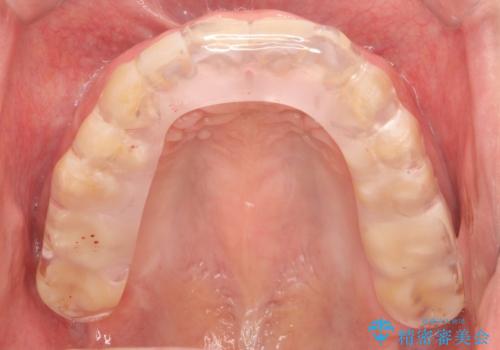

- 夜間の歯ぎしりを指摘されたことでナイトガード作成を希望して来院された患者様です。

厚いナイトガードでかみ合わせを微調整していきます。

全ての歯が均等に噛み合うよう調整することで噛む力を分散させ、一本の歯に噛む力が集中しないようにします。